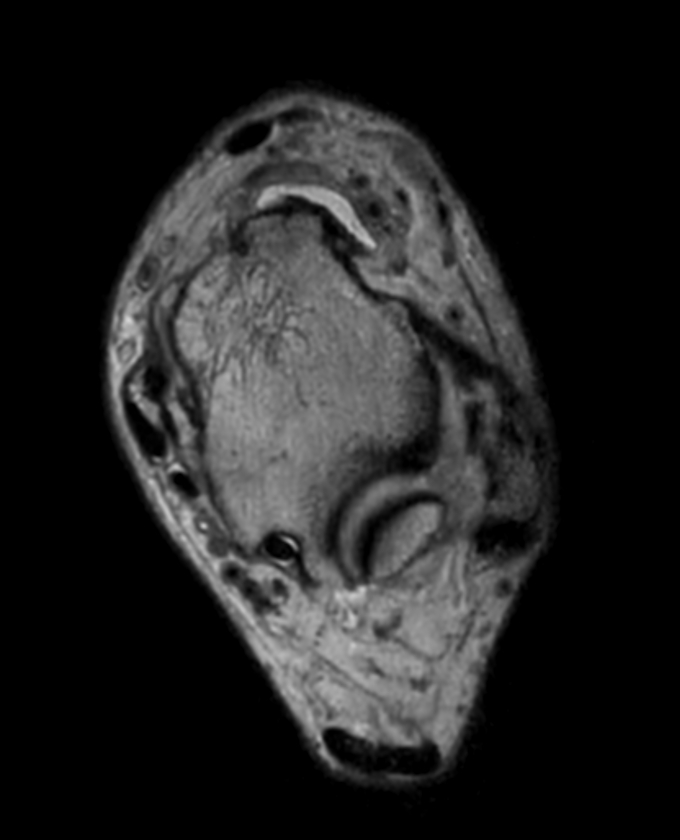

Axial 3D PDw MSK VIEW

Axial T2w TSE